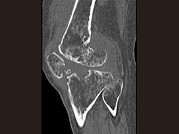

- 单项选择题男,36岁, 膝关节疼痛8年余,活动受限, 其周围可触及肿块,结合图像, 最可能的诊断是 ( )

A、骨巨细胞瘤

B、滑膜肉瘤

C、血友病性关节炎

D、色素沉着绒毛结节性滑膜炎

E、类风湿关节炎